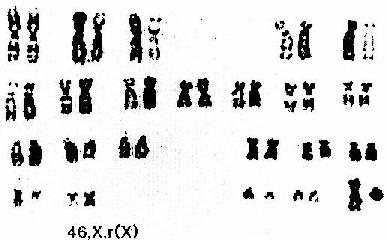

(5)Turner综合征:这是唯一已知的性染色体单体病(sex chromosome monosomy)。也称先天性卵巢发育不全症。典型核型是45,X。表型特征有:身材矮小,颈蹼及指、趾背部浮肿,为胎儿期淋巴水肿的残迹。后发际低、盾状胸、肘外翻,卵巢发育不全、原发闭经,性器官幼稚型(图6-6)。

图6-6 Turner综合征的一种核型 46,X,r(X)

由于一条X染色体呈环形,末端片段有丢失,影响卵巢发育